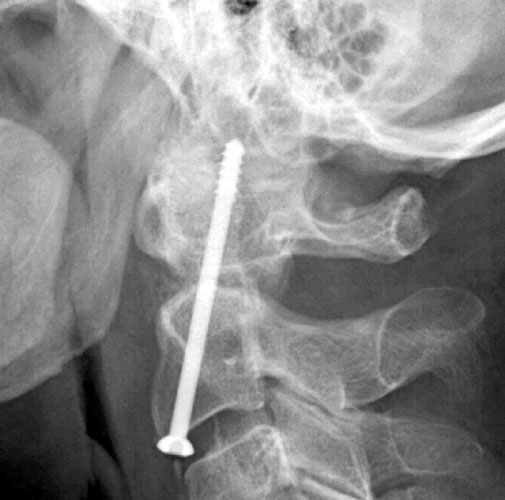

Lateral

radiograph obtained one day after surgery to assess for adequacy of

reduction and screw placement. The

film shows a threaded fixation screw coursing from the inferior endplate

of C-2 up through the tip of C2 with only two of the threads actually

within cortex with at least 8 mm of hardware protruding beyond the cortex

of C2 superiorly and the degree of protrusion posteriorly into the canal

appears to be 5 mm at its greatest extent. |